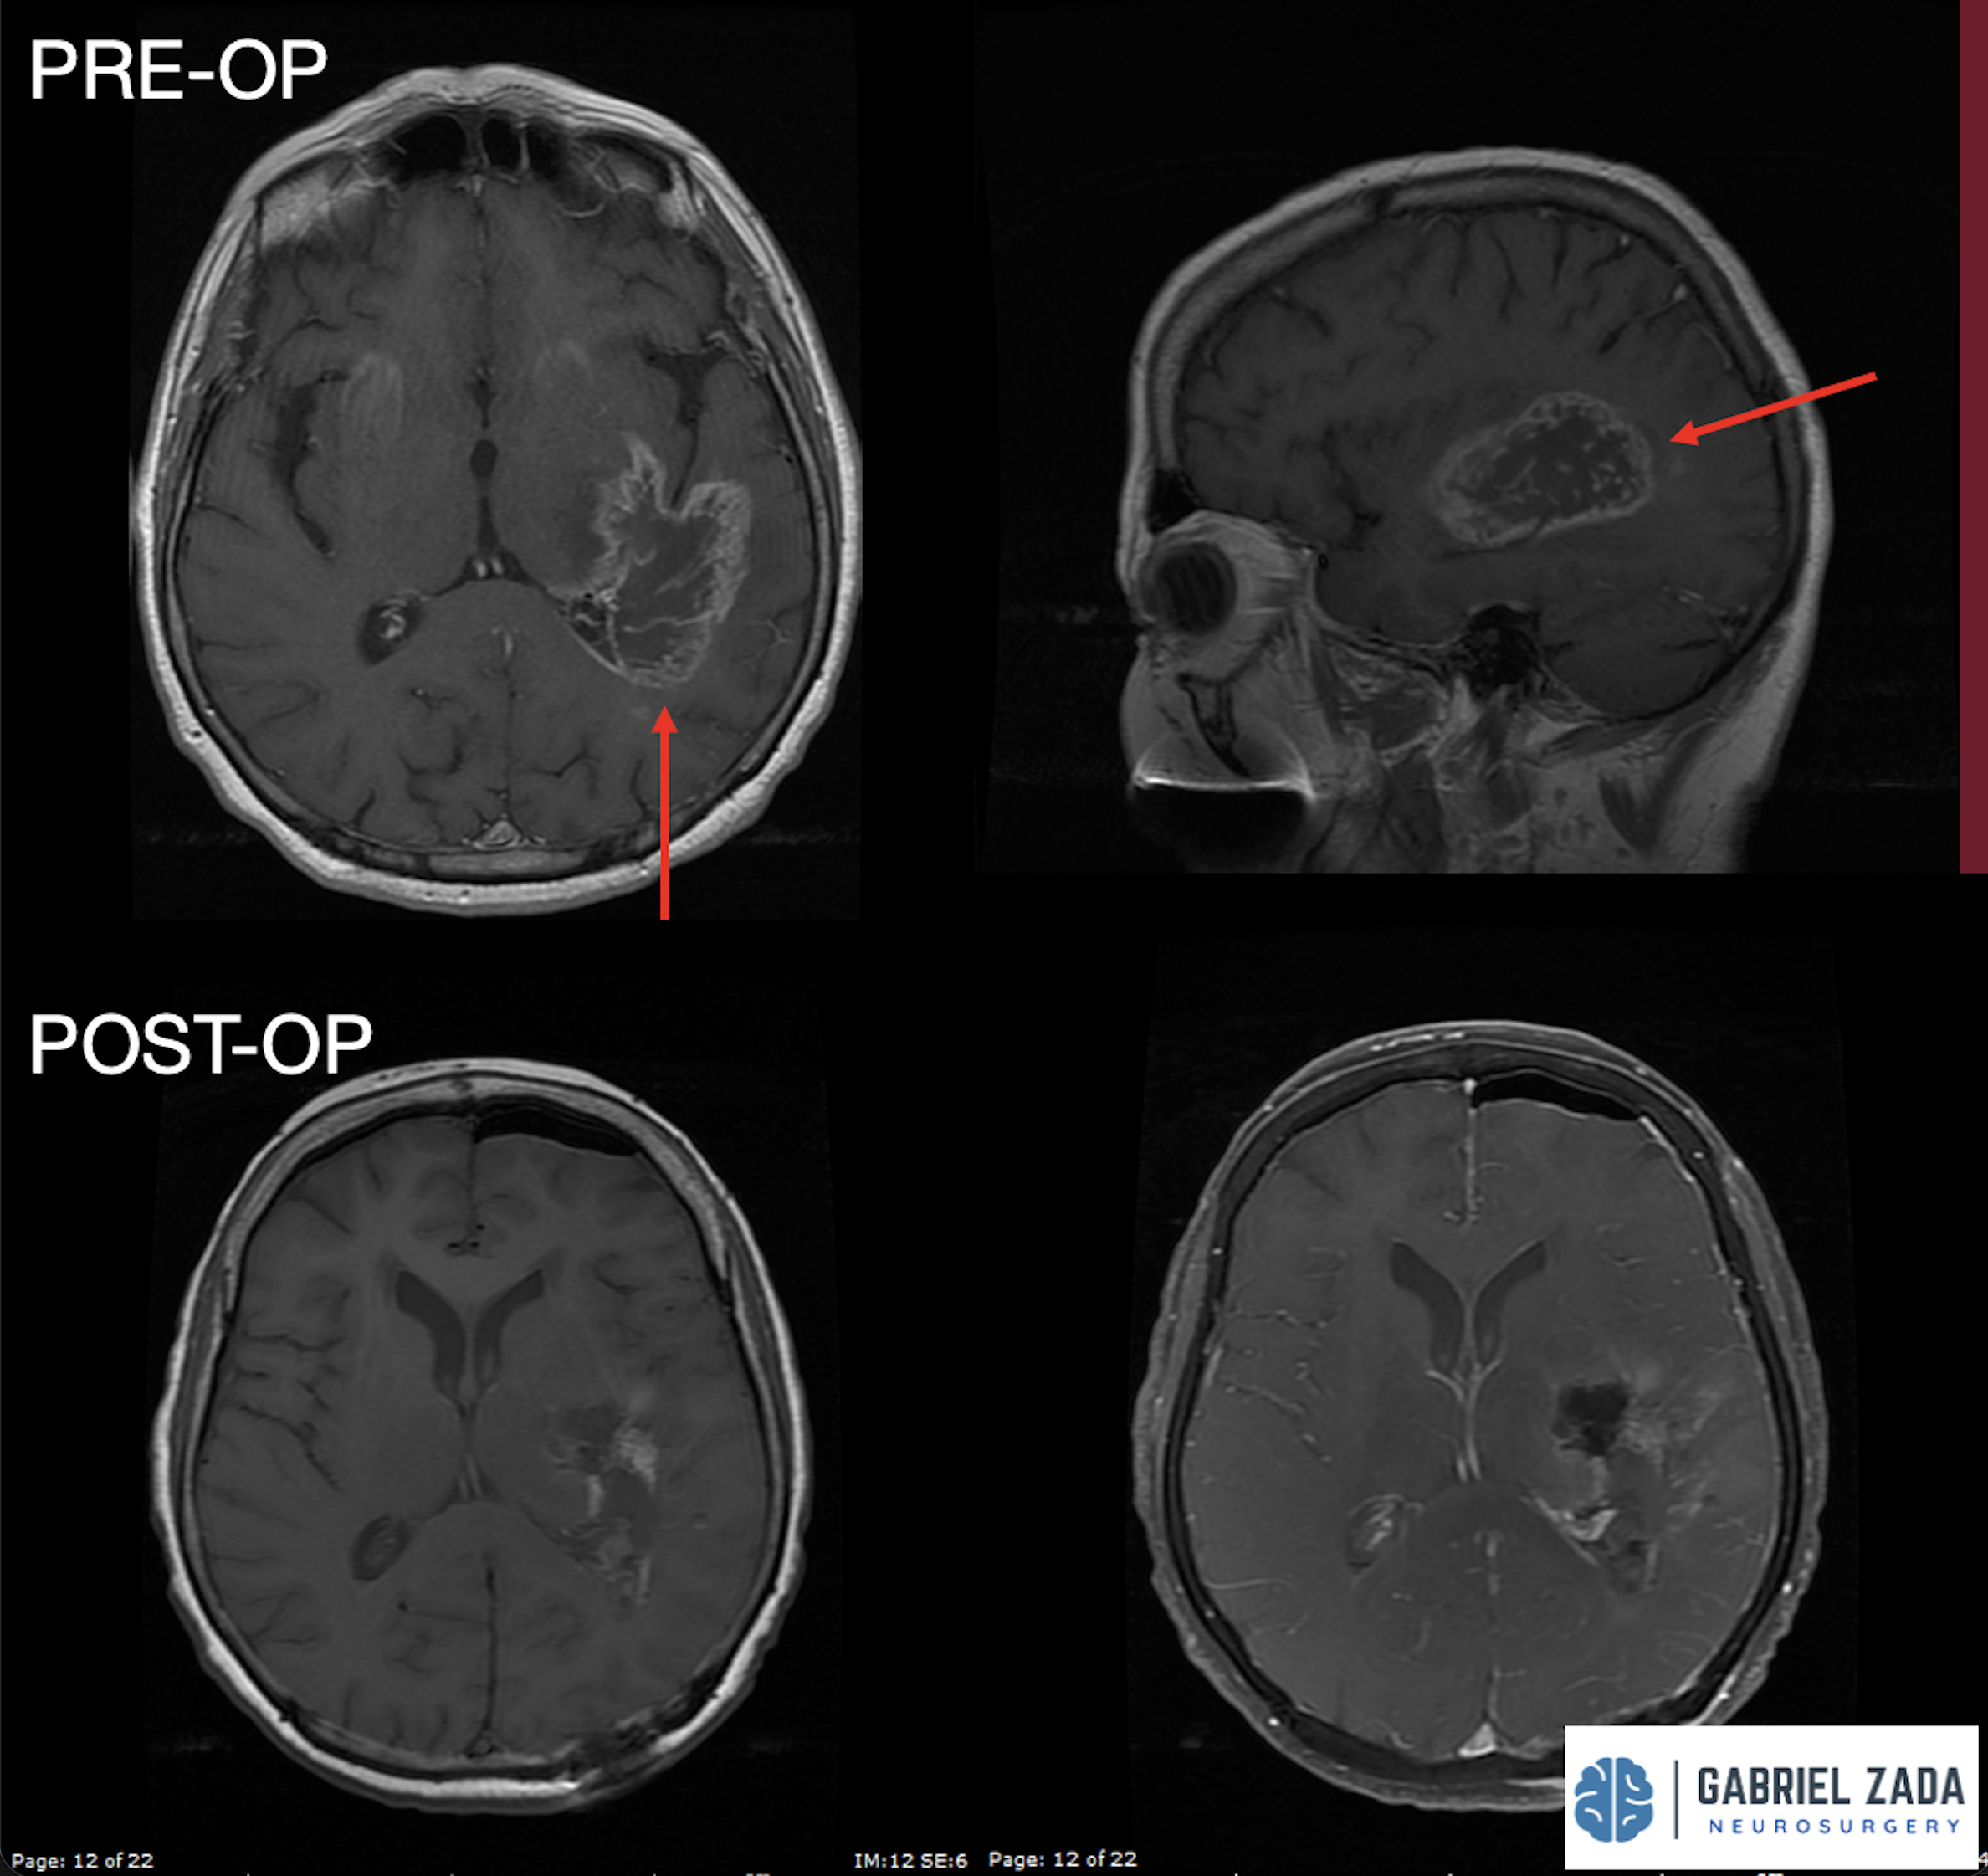

Explore this comprehensive gallery featuring pre‑ and post‑operative imaging of patients with skull‑base tumors treated by Gabriel Zada, MD, MS, FAANS, FACS. These cases highlight Dr. Zada’s expertise in advanced neurosurgical techniques and outcomes.

*Representative cases shown for educational purposes. All images de-identified. Individual results vary.